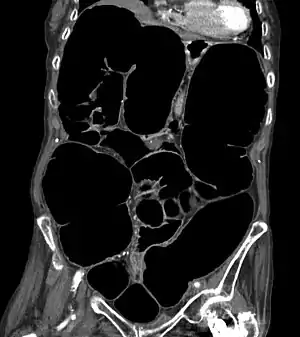

| CT-Scan showing a coronal section of the abdomen of an elderly woman with Ogilvie syndrome | |

Acute colonic pseudo-obstruction is characterized by massive dilatation of the cecum (diameter > 10 cm) and right colon on abdominal X-ray.[2][3] It is a type of megacolon, sometimes referred to as "acute megacolon," to distinguish it from toxic megacolon.